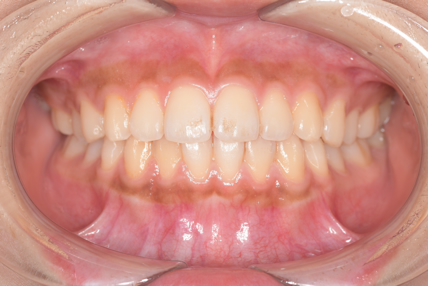

CASE 3

Before

After

基本情報

| 年齢・性別 | 30代・女性 |

| 主訴 | 定期検診 |

| 治療内容 | PMTC |

| 治療期間 | 60分 |

| 治療費 | 5,750円 |

| リスク・副作用 | しみる可能性があります。 |

| 治療方針 | PMTCでステインの除去。 |

| 担当者所見 | ステインが付きやすいため、3カ月毎の定期検診で除去する。 |